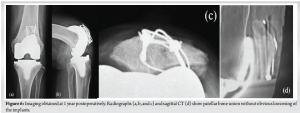

An 85-year-old female visited our hospital complaining of left knee pain. She had undergone ORIF with tension band wiring (TBW) for a left patellar fracture 7 months previously at a different hospital. However, bone union of the patellar fracture had not been achieved and the left knee pain persisted. She had a history of right patellar fracture and fractures of both ankles. Her body mass index was 25.6 kg/m2 (height, 157 cm; weight, 63.0 kg). Because of the left knee pain, she needed support for walking indoors and used a wheelchair outdoors. On physical examination, the range of motion (ROM) of the left knee was 0–120°. The pain was present at the medial joint space and around the patella, where it was particularly severe, with a Numerical Rating Scale (NRS; 0–10) of 8. Both of these areas were tender on palpation. No ligamentous instability was observed. Her Knee Society (KS) knee score was 53, and her KS function score was 40. Bone mineral density of the lumbar spine and proximal femur were 1.305 g/cm² and 0.678 g/cm², respectively. Radiographs of the left knee showed non-union of the patellar fracture, no joint space at the patellofemoral or medial femorotibial joints, and evidence of OA at the level of Kellgren–Lawrence classification stage IV at both of these sites (Fig. 1). Computed tomography (CT) of the left knee also showed non-union at the middle of the patella (Fig. 2). The femorotibial angle was 179°. There was no obvious implant failure of TBW. The diagnosis was severe knee OA with patellar non-union after a previous ORIF. As treatment for the patellar non-union and bone fragility, we initially treated the patient with low-intensity pulsed ultrasound (LIPUS) (Exogen Ultrasound Bone Healing System; Bioventus, Durham, NC) and teriparatide injection (Teribone; Asahi Kasei Pharma, Tokyo, Japan). LIPUS (1.5 MHz) was applied to the affected area for 15 min every day. As there was insufficient improvement in both the subjective symptoms and imaging findings in the left knee after 1 year of treatment, we decided to perform TKA and surgery for non-union of the patella in a one-stage procedure.

Surgery was performed under general anesthesia with a tourniquet. The previous skin incision was used and extended, and a medial parapatellar arthrotomy was performed. First, the femoral and tibial implants were replaced. An Attune knee system (DePuy Synthes, Warsaw, IN) with a fixed-bearing posterior cruciate-stabilizing prosthesis was used. The surgical epicondylar axis was used as the index for the rotation of the femoral component, and the Akagi line for the rotation of the tibial component. The cartilage of the patellofemoral joint was completely absent. The non-union fracture line was observed on the articular surface of the patella (Fig. 3). Next, surgery for non-union of the patella was performed. We removed the surgical wires of TBW, leaving the straight steel wires in place, and debrided the pseudarthrosis on the anterior surface of the patella using a Surgairtome. The debrided area of the pseudarthrosis was 10 × 20 mm. We transplanted autograft bone obtained from the TKA resection into this defect and performed a new TBW (AI-Wiring System; Aimedec MMT, Tokyo, Japan) (Fig. 4). The surgical wire used in the TBW firmly fixed the grafted bone. There was no bone fragment instability of the treated patellar non-union through 90° of knee flexion, and patellar tracking was acceptable. We decided not to perform patellar replacement because of concerns about bone loss due to OA and instability around the patellar non-union, even after the ORIF with bone grafting. To prevent ischemia of the patella, we also did not perform lateral release or lateral patellar facetectomy [5] (Fig. 5). Postoperatively, full weight-bearing walking was started 1 day after surgery. Knee immobilization with a brace was applied for 1 week. From the 2nd to 3rd week, the range of flexion gradually increased to 90°. After 3 post-operative weeks, the patient was allowed full ROM. At the 1-year follow-up, the patient was able to walk with a cane and the ROM of the left knee was 0–125° (0–120° preoperative). Her left knee pain decreased to 1 (8 preoperative) on the NRS. Patellar bone union was observed without obvious loosening of the implants (Fig. 6), and the KS knee score and function score had improved to 89 and 65 (53 and 40 preoperative), respectively. At the 2-year follow-up, her left knee pain was 0 on the NRS, and the KS knee score and function score were maintained.